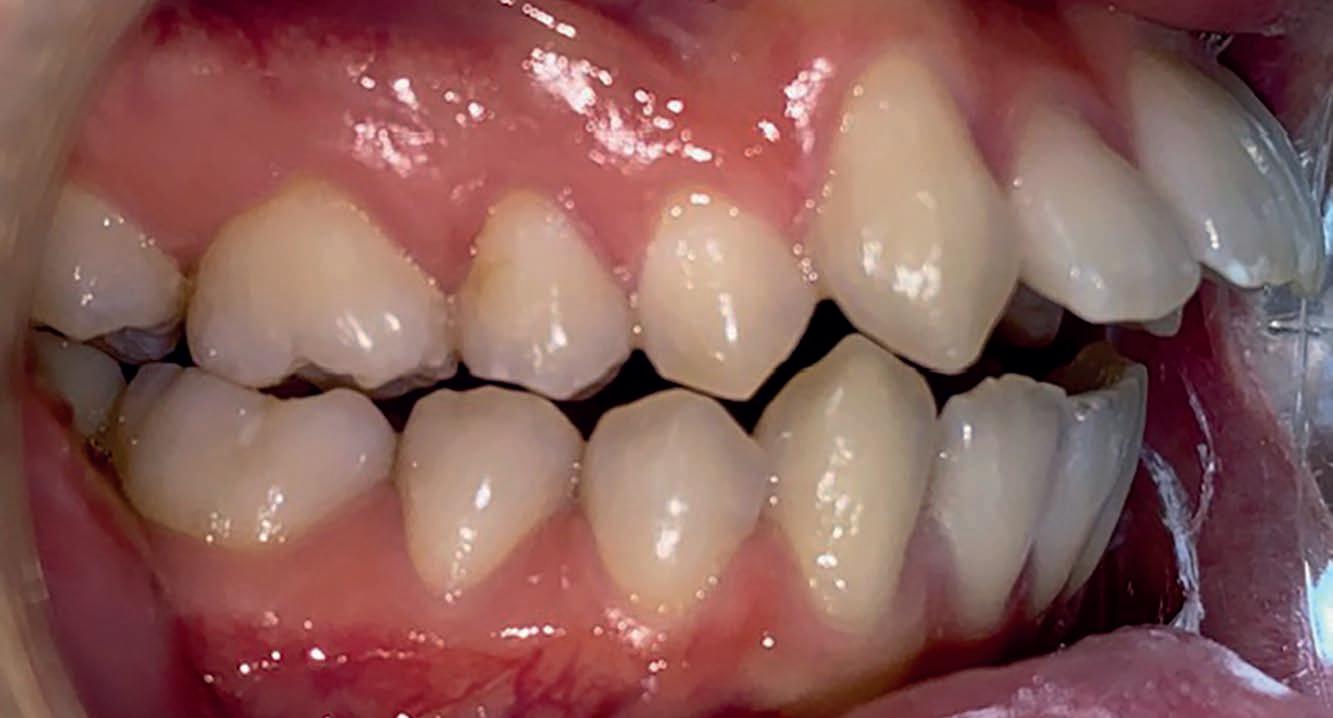

Casus: uit de Praktijk Sole & Jalissa.

Eén overbeet, twee gezichten

Sole en Jalissa kwamen op jonge leeftijd bij ons in de praktijk. Op het eerste gezicht leken hun gebitten totaal verschillend, maar achter de lach ging dezelfde afwijking schuil: een overbeet van 9–10 mm en versmalde tandbogen.

Bij Jalissa was de Klasse II-relatie direct zichtbaar: de bovenkaak stond duidelijk vóór de onderkaak en de lippen sloten moeilijk.

Bij Sole leek het minder opvallend. Haar bovenste snijtanden (11/21) stonden namelijk naar binnen gekanteld (Klasse II Divisie 2), waardoor de overbeet gecamoufleerd werd – maar de kaakrelatie was identiek.

Dit soort casussen laten zien waarom het belangrijk is om verder te kijken dan alleen de zichtbare tandstanden. Wat aan de buitenkant mild lijkt, kan functioneel en skeletaal net zo ernstig zijn.

Behandeling – starten met de juiste basis

Beide meisjes begonnen met een Twinblock-beugel, een functioneel apparaat dat de groei van de onderkaak stimuleert en de overbeet corrigeert. Ze droegen deze 9 tot 12 maanden.

Deze fase zorgde voor:

• Voorwaartse groei en positionering van de onderkaak

• Verbetering van de lip- en profielbalans

• Ruimte in de kaakbogen door natuurlijke verbreding

• Voorbereiding op een voorspelbaar verloop met vaste apparatuur (slotjesbeugel)

Na deze fase kan de slotjesbeugels efficiënt starten.

Waarom timing belangrijk is

Wij adviseren om een Twinblock te starten rond eind groep 6 of begin groep 7. In deze periode:

• is de groeispurt optimaal te benutten,

• is de motivatie hoger (voor middelbare school),

• en kan een operatie of complexe behandeling op latere leeftijd vaak worden voorkomen.

Te laat starten – bijvoorbeeld in de brugklas – betekent meestal minder groei, minder motivatie en grotere behandeluitdagingen.

Overbeet: 9 - 10 mm bij beide

Kaakrelatie: Klasse II (Jalissa)

Klasse II Div. 2 (Sole, 11/21 retrogekanteld)

Tandbogen: Versmald

Eerste behandeling: Twinblock, 9 - 12 maanden

Doel: Kaakrelatie corrigeren, profiel

verbeteren, ruimte creëren

Resultaat: Zachter profiel, betere balans, goede basis voor slotjesbeugel